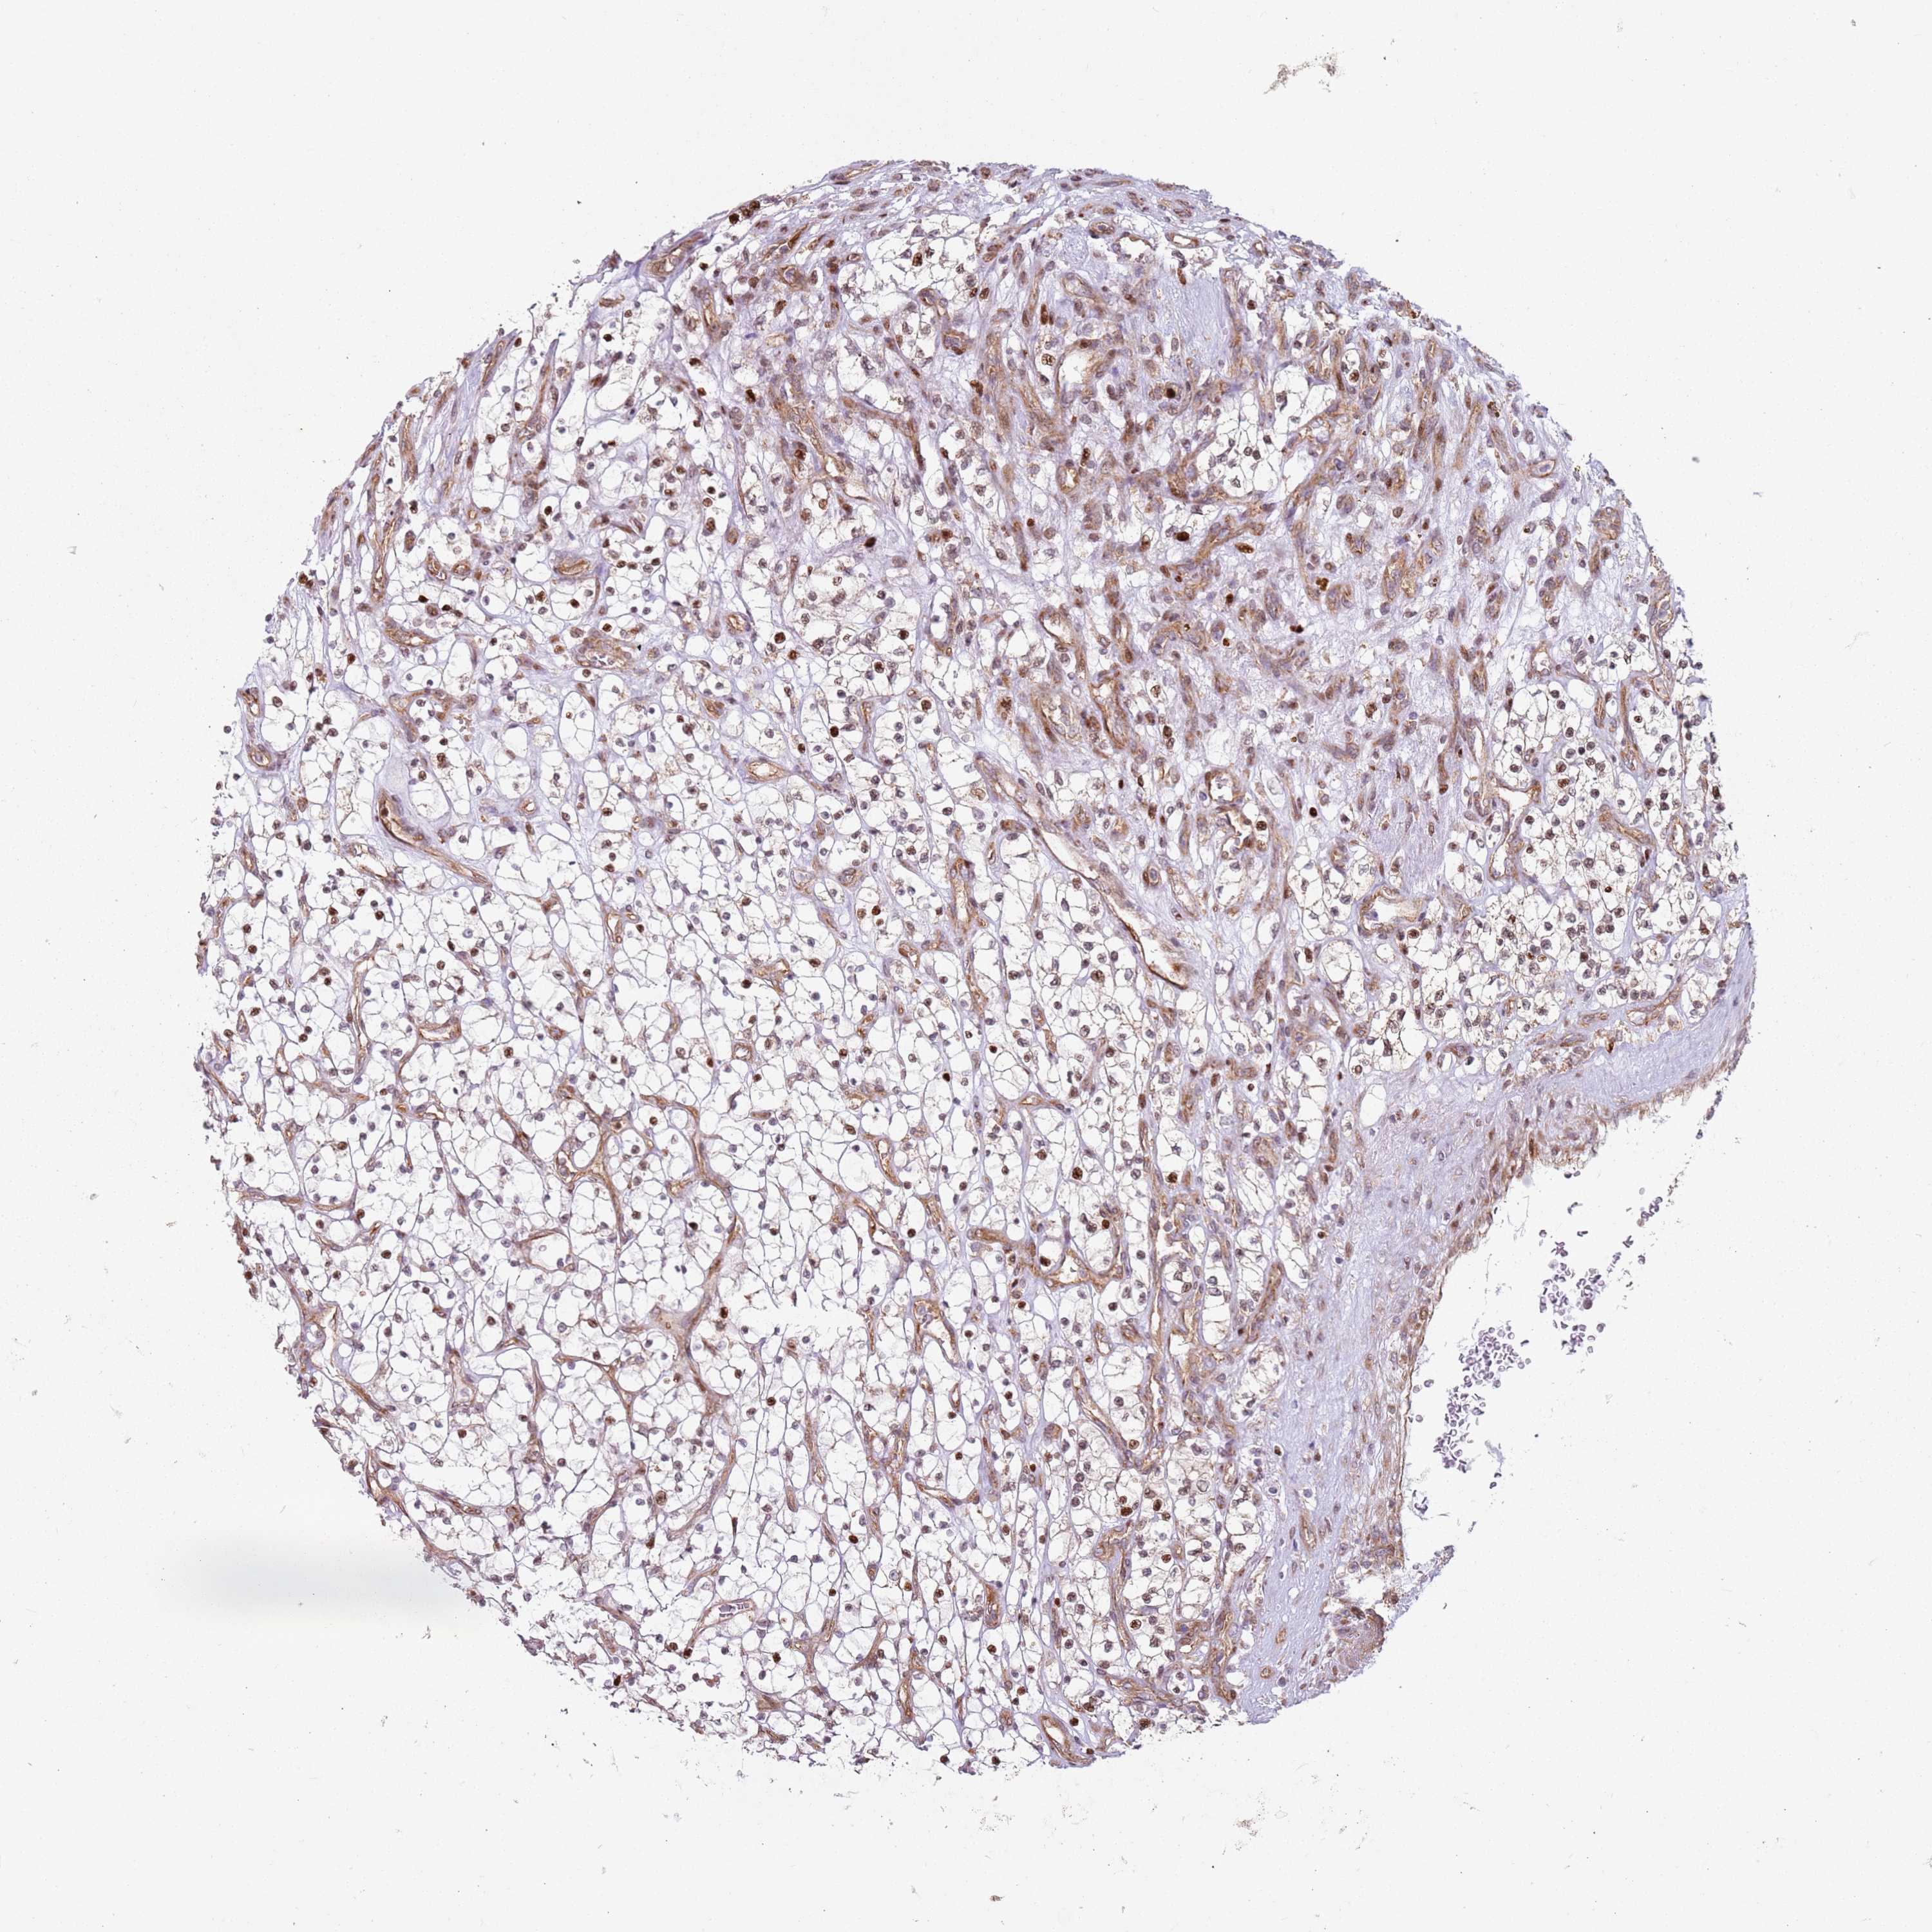

KIDNEY RENAL CLEAR CELL CARCINOMA (TCGA) - Interactive survival scatter ploti

The Survival Scatter plot shows the clinical status (i.e. dead or alive) for all individuals in the patient cohort, based on the same data that underlies the corresponding Kaplan-Meier plots. Patients that are alive at last time for follow-up are shown in blue and patients who have died during the study are shown in red.

The x-axis shows the expression levels (FPKM) of the investigated gene in the tumor tissue at the time of diagnosis. The y-axis shows the follow-up time after diagnosis (years). Both axes are complimented with kernel density curves demonstrating the data density over the axes. The top density plot shows the expression levels (FPKM) distribution among dead (red) and alive patients (blue). The right density plot shows the data density of the survived years of dead patients with high and low expression levels respectively, stratified using the cutoff indicated by the vertical dashed line through the Survival Scatter plot. This cutoff is automatically defined based on the FPKM cutoff that minimizes the p-score. The cutoff can be changed by dragging the vertical line or by entering a cutoff value in the square labeled "Current cut-off".

Under the Survival Scatter plot the p-score landscape (black curve; left axis) is shown together with dead median separation (red curve; right axis). Dead median separation is the difference in median mRNA expression between patients who have died with high and low expression, respectively. It is calculated as follows: median FPKM expression of dead patients with high expression - median FPKM expression of dead patients with low expression. This is intended to aid the user in visually exploring custom cutoffs and the associated p-scores and dead median separation.

Individual patient data is displayed and can be filtered by clicking on one or more of the category buttons on the top of the page. Categories describing expression level and patient information include: high, low, alive, dead, female, male and tumor stages. The scale of the x-axis can be toggled between linear and log-scale by clicking on the "x log" button. Mouse-over function shows TCGA ID, patient information and mRNA expression (FPKM) for each patient.

& Survival analysisi

Kaplan-Meier plots summarize results from analysis of correlation between mRNA expression level and patient survival. Patients were divided based on level of expression into one of the two groups "low" (under cut off) or "high" (over cut off). X-axis shows time for survival (years) and y-axis shows the probability of survival, where 1.0 corresponds to 100 percent.

HNRNPLL is potential prognostic, high expression is favorable in Kidney Renal Clear Cell Carcinoma (TCGA)

Best expression cut offi

Based on the FPKM value of each gene, patients were classified into two groups and association between prognosis (survival) and gene expression (FPKM) was examined. The best expression cut-off refers the FPKM value that yields maximal difference with regard to survival between the two groups at the lowest log-rank P-value. Best expression cut-off was selected based on survival analysis .

When clicking on this number, the vertical dashed line indicating cut-off, the interactive survival plot, and the Kaplan-Meier curve will be adjusted to show results based on the best expression cut-off.

: 9.31

P scorei

Log-rank P value for Kaplan-Meier plot showing results from analysis of correlation between mRNA expression level and patient survival.

N/A

5-year survival highi

5-year survival for patients with higher expression than the expression cutoff.

For melanoma and glioma, 3-year survival is shown.

5-year survival lowi

5-year survival for patients with lower expression than the expression cutoff.

TCGA RNA samplesi

RNA-seq data is reported as average FPKM (number Fragments Per Kilobase of exon per Million reads), generated by the The Cancer Genome Atlas (TCGA) .

Normal distribution across the dataset is visualized with box plots, shown as median and 25th and 75th percentiles. Points are displayed as outliers if they are above or below 1.5 times the interquartile range. FPKM values of the individual samples are presented next to the box plot.

Average pTPM 13.8

Number of samples 521